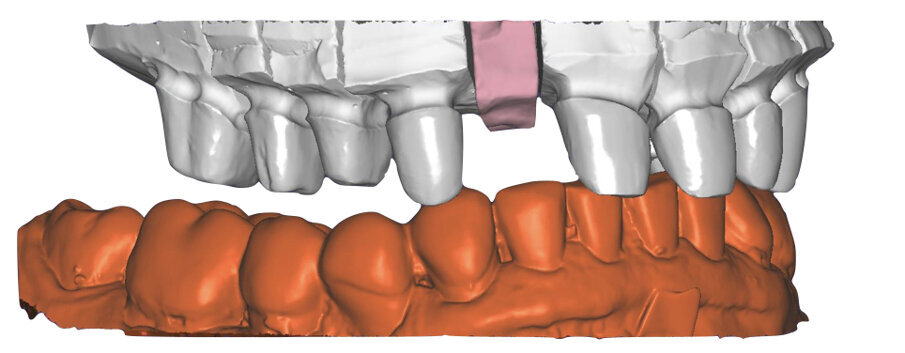

I modelli sono così importati in corretta posizione spaziale tramite il modulo exocad Virtual Articulator (Fig. 25). Non avendo a disposizione nel CAD l’analogo virtuale dell’articolatore Reference SL, viene impostato il sistema virtuale SAM, che usa lo stesso piano di riferimento axio-orbitale e geometria sovrapponibile al Reference SL. Per la programmazione virtuale dei parametri funzionali dell’articolatore si riesegue l’output dall’axiografia elettronica con Gamma Dental per SAM (Fig. 26). Si procede perciò ora con la modellazione CAD della ceratura mantenendo il riferimento dato dal piano occlusale individuato dai coni di centrica scansiti con l’articolatore (Fig. 27). L’articolatore virtuale consente una prima verifica dei rapporti occlusali tra gli elementi e un abbozzo di funzionalizzazione delle cuspidi con strumenti virtuali dinamici, che permette di arrivare ad un CAD design vicino alla morfologia ricercata (Figg. 28-33). Il modellato è ora fresato in cera Yeti Dental al CAM con fresatore VHF Cam5-S1 ed i denti in cera, tutti singolarmente sfilabili, sono posizionati sui modelli eseguiti con stampa 3D.

Il paziente utilizza questi secondi provvisori per otto settimane, durante le quali conferma la buona integrazione dei restauri e la soddisfacente funzione occlusale. Ciò è verificato con l’esecuzione di una nuova axiografia elettronica che già a due settimane dalla consegna evidenzia una buona risposta muscolare al nuovo design occlusale ed alla nuova postura mandibolare in TRP (Figg. 43-46). Provvediamo infine alle impronte per la costruzione dei manufatti definitivi in Zirconia-ceramica. I modelli sono scansiti in laboratorio con inEos X5 (Dentsply Sirona) su exocad (Figg. 47-49), ed una seconda scansione viene eseguita con i provvisori del Paziente posizionati sui modelli (Figg. 50-52). Il CAD consente di eseguire un matching fra le due scansioni, per cui i secondi provvisori utilizzati in TRP, con funzione occlusale sequenziale già completamente programmata, sono utilizzati per definire le morfologie dentali definitive di tutti gli elementi da restaurare (Figg. 53, 54) secondo il rapporto intermascellare definito (Figg. 55-58). Si esegue quindi fresatura al CAM della protesi definitiva in zirconia (Figg. 59, 60), la stratificazione e finitura ed infine la consegna al Paziente con cementazione in Panavia V5 (Figg. 61-65).